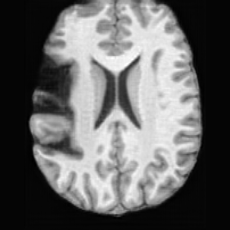

PathologicalSynthSR [18]Brain-ID [28]UNA [30]USBRefer to captionRefer to captionRefer to captionRefer to captionRefer to captionRefer to captionRefer to captionRefer to captionRefer to captionRefer to caption

Figure D.1: Comparison of pathology-to-healthy editing results on real stroke brain images from the ATLAS dataset [27].

Editing as Healthy Reconstruction for Patient Scans. Fig. D.1 illustrates the results of different methods applied to real stroke pathological brain images from the ATLAS dataset [27]. As shown, for relatively small lesions (first row), competing methods can partially reconstruct healthy brain structures, yet the results are noticeably inferior to those produced by USB. For larger lesions (second row), all other methods fail to recover the healthy regions, whereas USB successfully restores anatomically plausible healthy brain structures. These observations demonstrate USB’s superior ability to handle a wide range of lesion sizes and its robustness in generating anatomically plausible healthy reconstructions from real pathological scans, even though the model was trained solely on pseudo-synthetic pathological data.